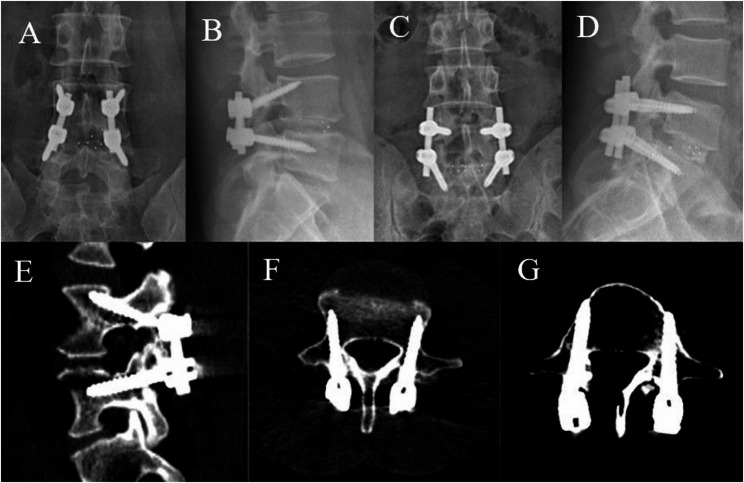

Results: Basic demographic data, fusion rates, postoperative hospital stays, and follow-up times did not significantly differ between the two groups. Compared with those in the M-TLIF group, the intraoperative blood loss (68.57 ± 14.84 mL) and postoperative drainage volume (33.93 ± 9.17 mL) in the M-MIDLIF group were lower (intraoperative blood loss: 171.79 ± 12.78 mL, p < 0.05; postoperative drainage volume: 65.36 ± 10.36, p < 0.05). In the M-MIDLIF group, there was no significant difference in the radiographic recognizable rate (91.07%) or intraoperative visual recognizable rate (87.50%) of internal inverted chevron-shaped (V-shaped) crests. The optimal position screw rates for the MCBT, TASS, and traditional pedicle screw (TPS) methods were 94.64%, 94.64%, and 87.5%, respectively, and the differences were not significant. MCBT technology preserved the integrity of the posterior ligamentous complex (PLC) in 92.85% of patients in the M-MIDLIF group. The facet joint violation (FJV) rate of MCBT screws (3.57%) was lower than that of TPS screws (14.29%). Compared with the M-TLIF group, the M-MIDLIF group presented greater reductions in the ODI and VAS scores for both low back and leg pain at 1 week postoperatively (P < 0.05). However, no statistically significant differences in these scores were observed between the two groups at later time points (p > 0.05).